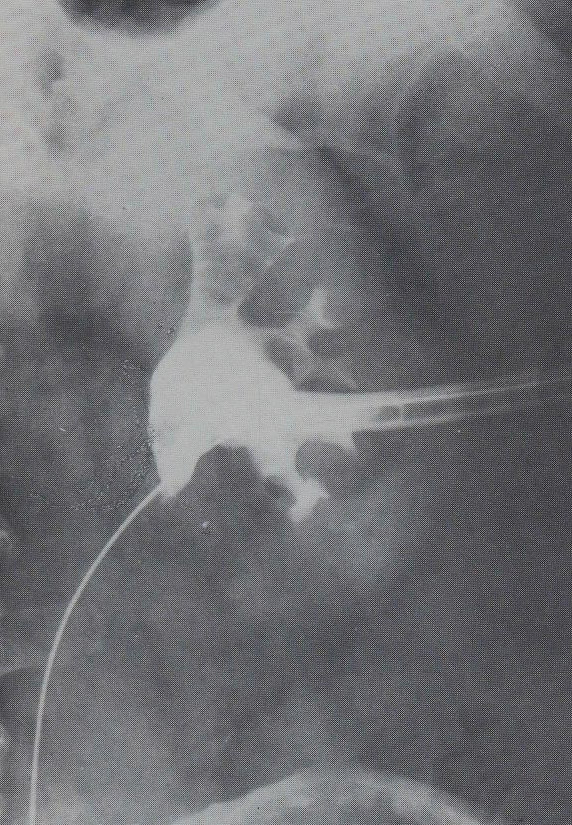

19.5.1. Percutaneous transhepatic cholangiogrpahy (PTC)

During this procedure X-ray or US is used to guide the insertion of a 22G (Chiba needle) from a right IX. or X. intercostals position into a dilated intrahepatic biliary branch. After the Chiba needle is well positioned the intra and extrahepatic biliary tree is filled with contrast material. (Figure 21.)

Image

Figure 21. – PTC (Percutaneous transhepatic cholangiography)